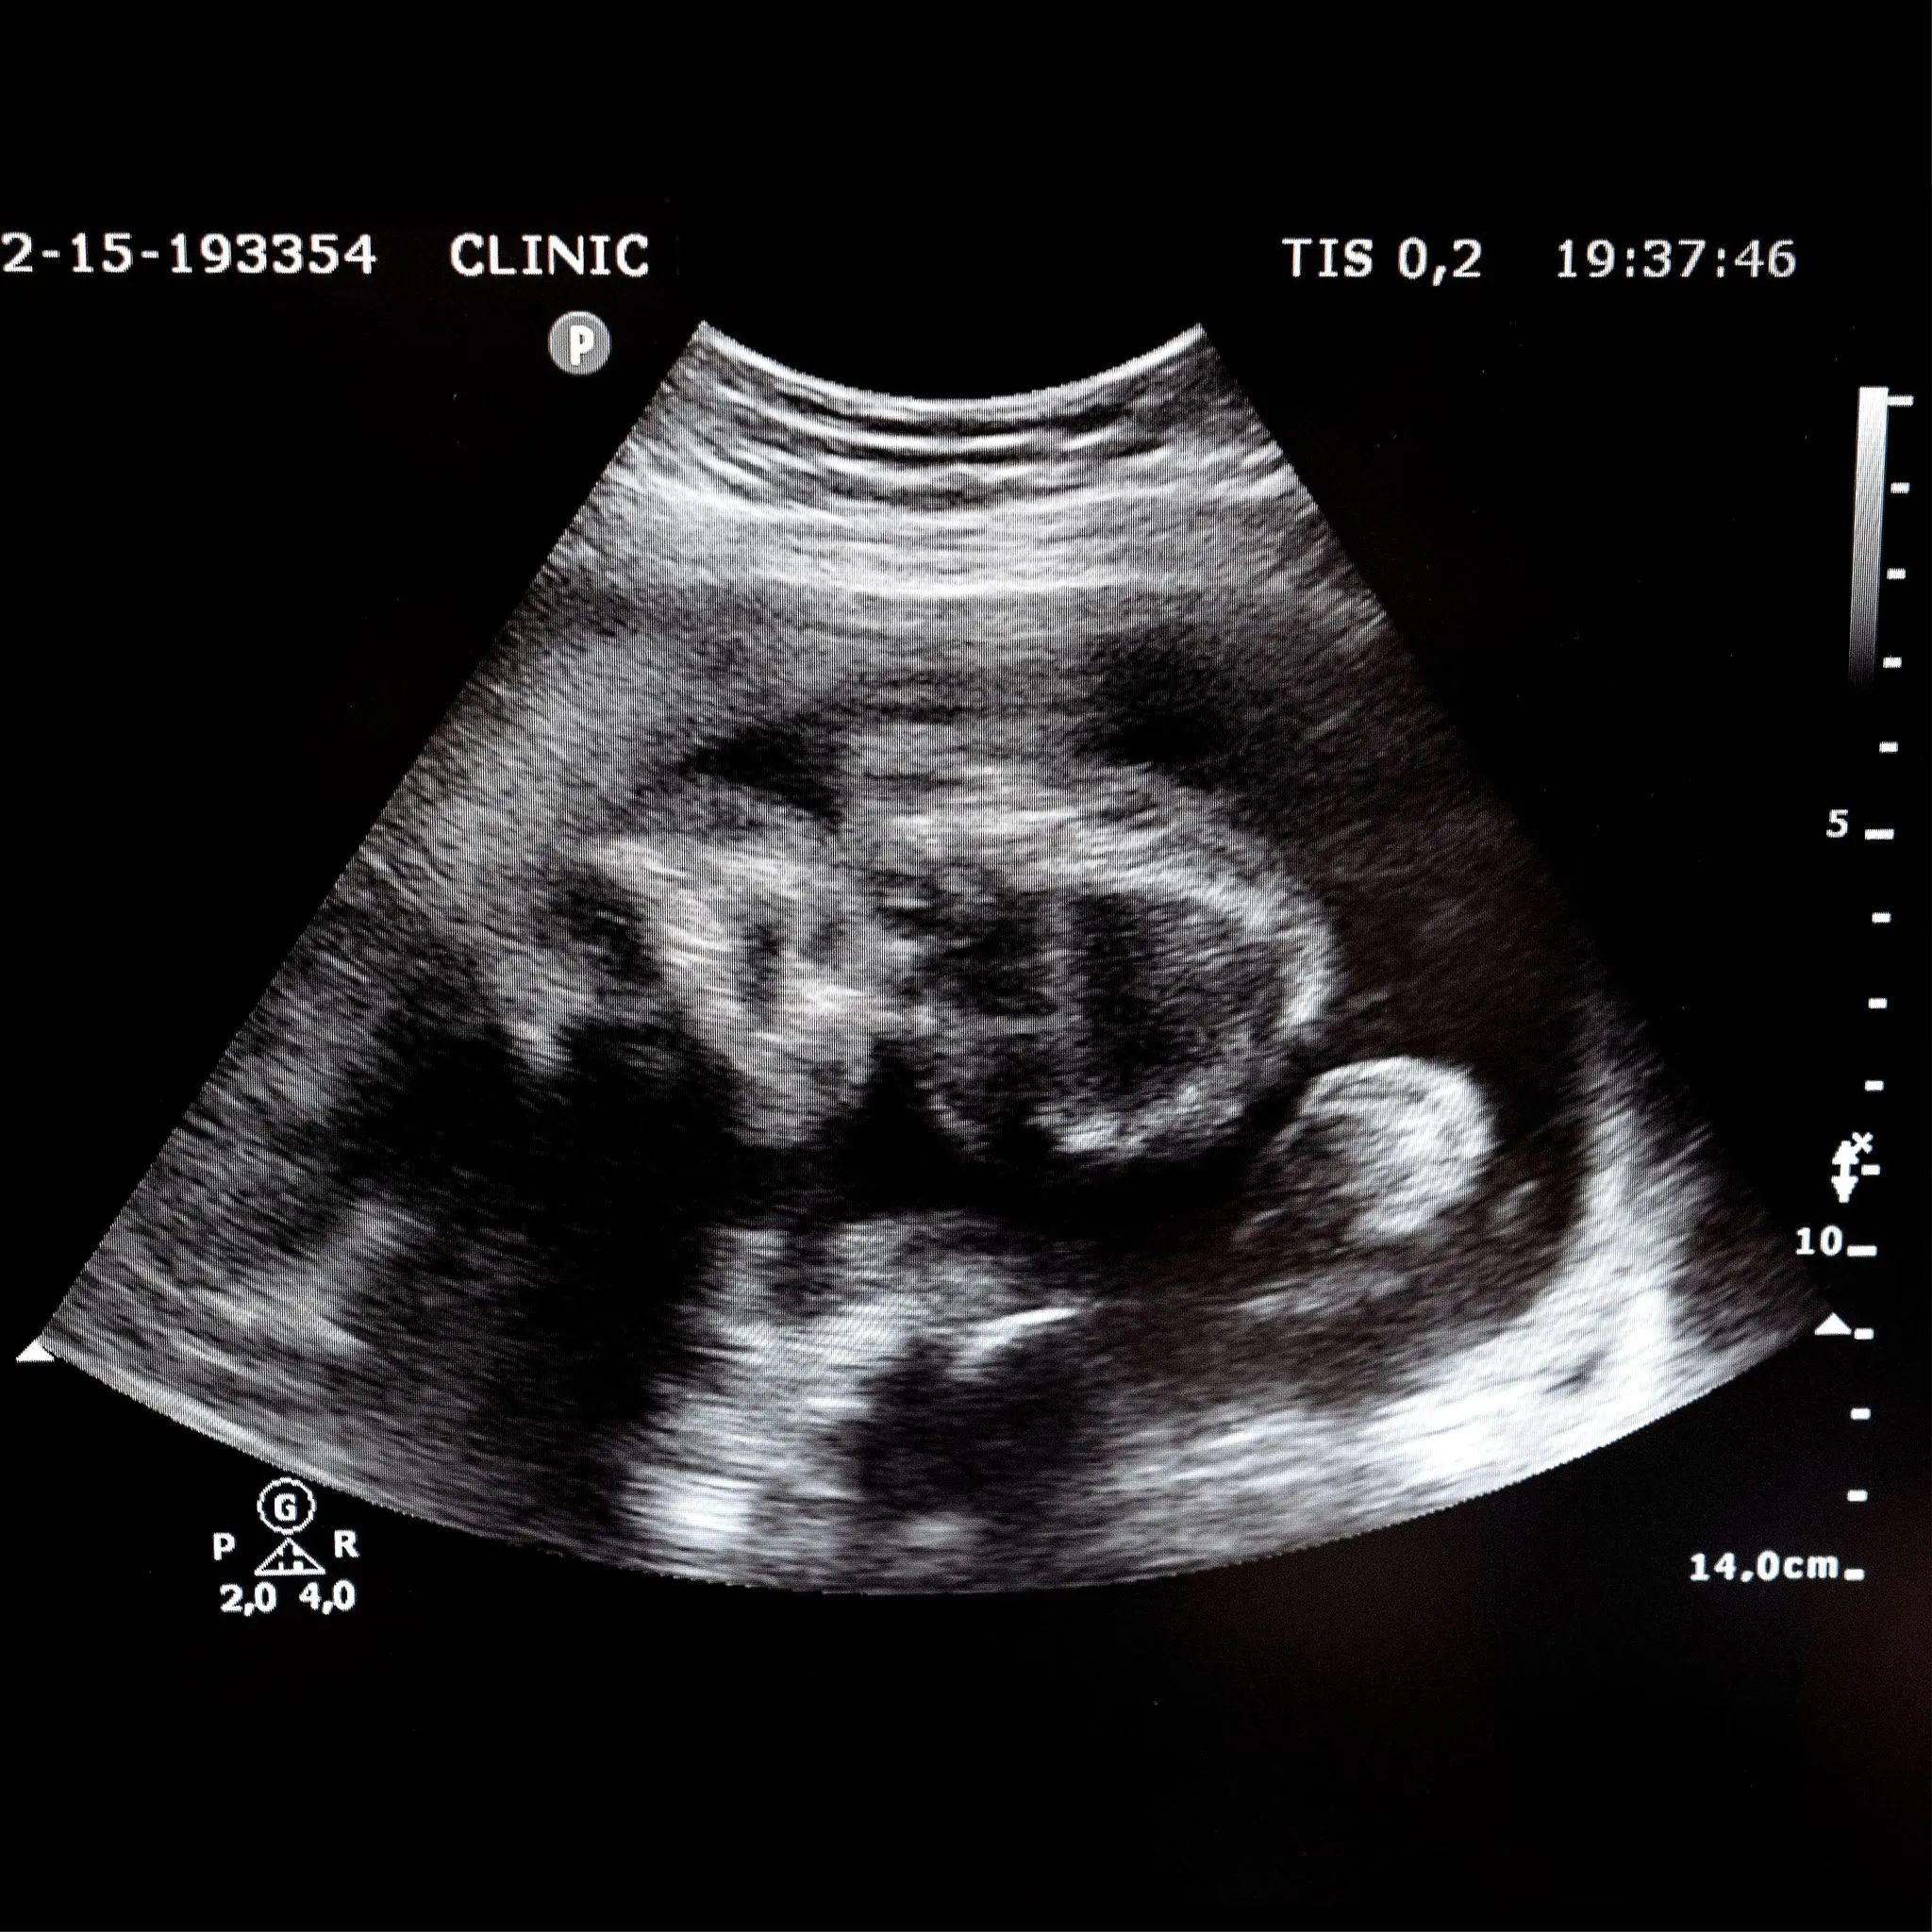

L’impact des fréquences sonores sur le vivant n’est plus à démontrer. Les êtres humains, les animaux, les arbres et les plantes sont réceptifs à la musique et aux vibrations de la voix. Depuis la vie intra-utérine, le son accompagne le développement de l’enfant : le fœtus baigne dans un univers sonore - celui du ventre de sa mère - et contacte le monde extérieur à travers les vibrations qu’il perçoit. Une étude française de 2007 a apporté la preuve que “dans le ventre de sa mère, le fœtus associe sons et émotions“. Avec les Baumes sonores, une nouvelle voie thérapeutique se dessine pour accompagner le développement du nouveau-né.

Depuis la vie intérieure du corps humain, émane une véritable symphonie vibratoire. Les différents systèmes digestif, circulatoire et cardiaque, forment un ensemble orchestral complexe, composé de tuyaux et de conduits de longueurs variées qui, à l’image des orgues des cathédrales, émettent des sons en continu : une symphonie du dedans que le fœtus est en mesure de percevoir in utero dès le 7e mois de gestation, avec le développement de la cochlée1 dans l’oreille interne. Selon de récentes études, ce bruit de fond représenterait un niveau sonore d’environ 30 décibels : l’équivalent d’un chuchotement… Or, si le fœtus dispose d’une audition quasi-normale à partir de cette période, il a été démontré qu’il était sensible aux bruits avant cela, dès la 25e semaine. Ainsi, au-delà de cette symphonie intérieure, le fœtus est capable d’entendre certains sons extérieurs, plus lointains, tels que les voix, la musique, les bruits provenant de l’environnement…

Habitué à la voix de sa mère, il perçoit mieux cependant les fréquences basses - comme la voix de son père - et les notes graves, qui renforcent son ancrage à la terre. Lorsqu’il vient au monde, le nouveau-né garde une empreinte des sons perçus durant la période de gestation. Cette mémoire auditive, en apportant au nourrisson des repères connus et rassurants, facilite la transition entre la vie in utero et son entrée dans le monde du dehors. Dès lors, il est plus facile de comprendre l’influence des fréquences sonores sur le bien-être et la santé de l’enfant. Ceci explique également l’intérêt qu’elles suscitent auprès de nombreux chercheurs, ainsi que l’émergence de nouvelles approches thérapeutiques.